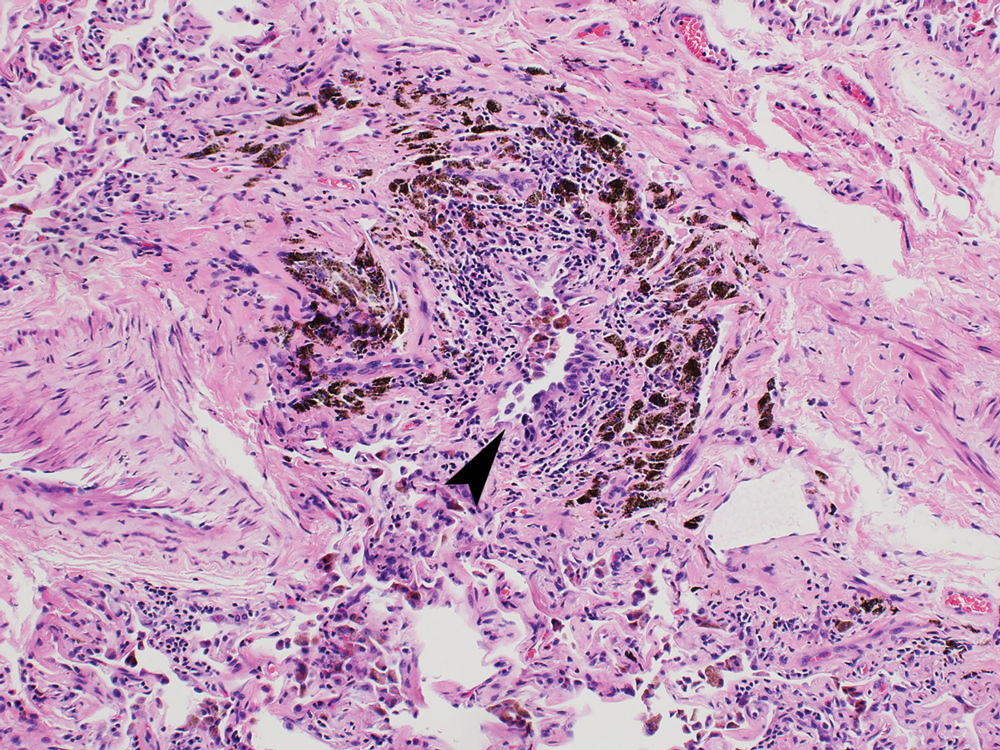

Figure 4. Photomicrograph in a 52-year-old man with polysubstance abuse, including marijuana. Intermediate-power magnification of lung tissue shows a destroyed bronchiole, with only a slit-like lumen (arrowhead) remaining and heavy black carbon deposits. (Hemotoxylin-eosin stain; original magnification, ×100.) (Galvin and Franks)